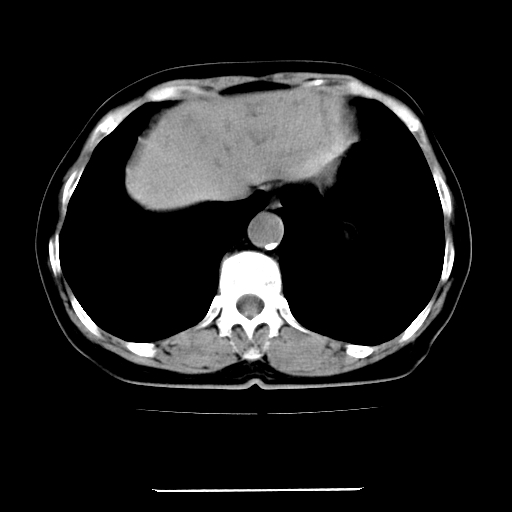

标题: CT22301:女,67岁,上腹部疼痛一周伴皮肤黄染,无发热。 [打印本页]

女,67岁,上腹部疼痛一周伴皮肤黄染,无发热。

左叶肝内胆管结石,并远端肝内胆管扩张。

考虑:肝内胆管结石继发肝内胆管扩张,右肾旋转不良。

支持肝内胆管结石并肝内胆管扩张。

肝内外胆管结石并肝内胆管扩张。

建议薄层观察,除外肝门部胆管细胞癌

考虑肝胆管癌;胰头占位?【形态失常,体积增大】

1、肝门高密度影下层面和胰头层面可见轻度胆管扩张,而静脉和延迟期均未见扫描完胰头,不能完全排除胰头占位。2、肝门部高密度影,考虑钙化或结石。

考虑肝门胆管癌伴门脉左支受侵包埋,建议mrcp进一步检查。